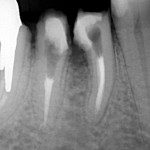

Jeśli przeleczony kanałowo ząb jest wrażliwy a zdjęcie rentgenowskie wykazuje defekt kostny w obrębie bifurkacji  czyli w miejscu rozdzielenia korzeni, wszystko wskazuje na to, że dno komory zęba jest zniszczone, a nieszczelnośc ta spowodowała zniszczenie kości w tym miejscu. Zachowawcze leczenie jest niemożliwe.

Jeśli chce się uratowć taki ząb, jedynym rozwiązaniem jest separacja czyli premolaryzacja. Zabieg ten wykonuje się w znieczuleniu miejscowym. Wiertłem przecina się ząb, tak by odsłonić całą perforację dna komory. Stwarza się w ten sposób dwa oddzielne zęby. Miejsce przecięcia należy bardzo dokładnie i szczelnie zabezpieczyć kompozytem. Jest to dość trudne w wilgotnym, podziąsłowym miejscu. Jeśli leczenie kanałowe jest nieszczelne należy je wykonać ponownie.

Poniżej zdjęcie rentgenowskie po zabiegu premolaryzacji. Widzimy już dwa oddzielne zęby.